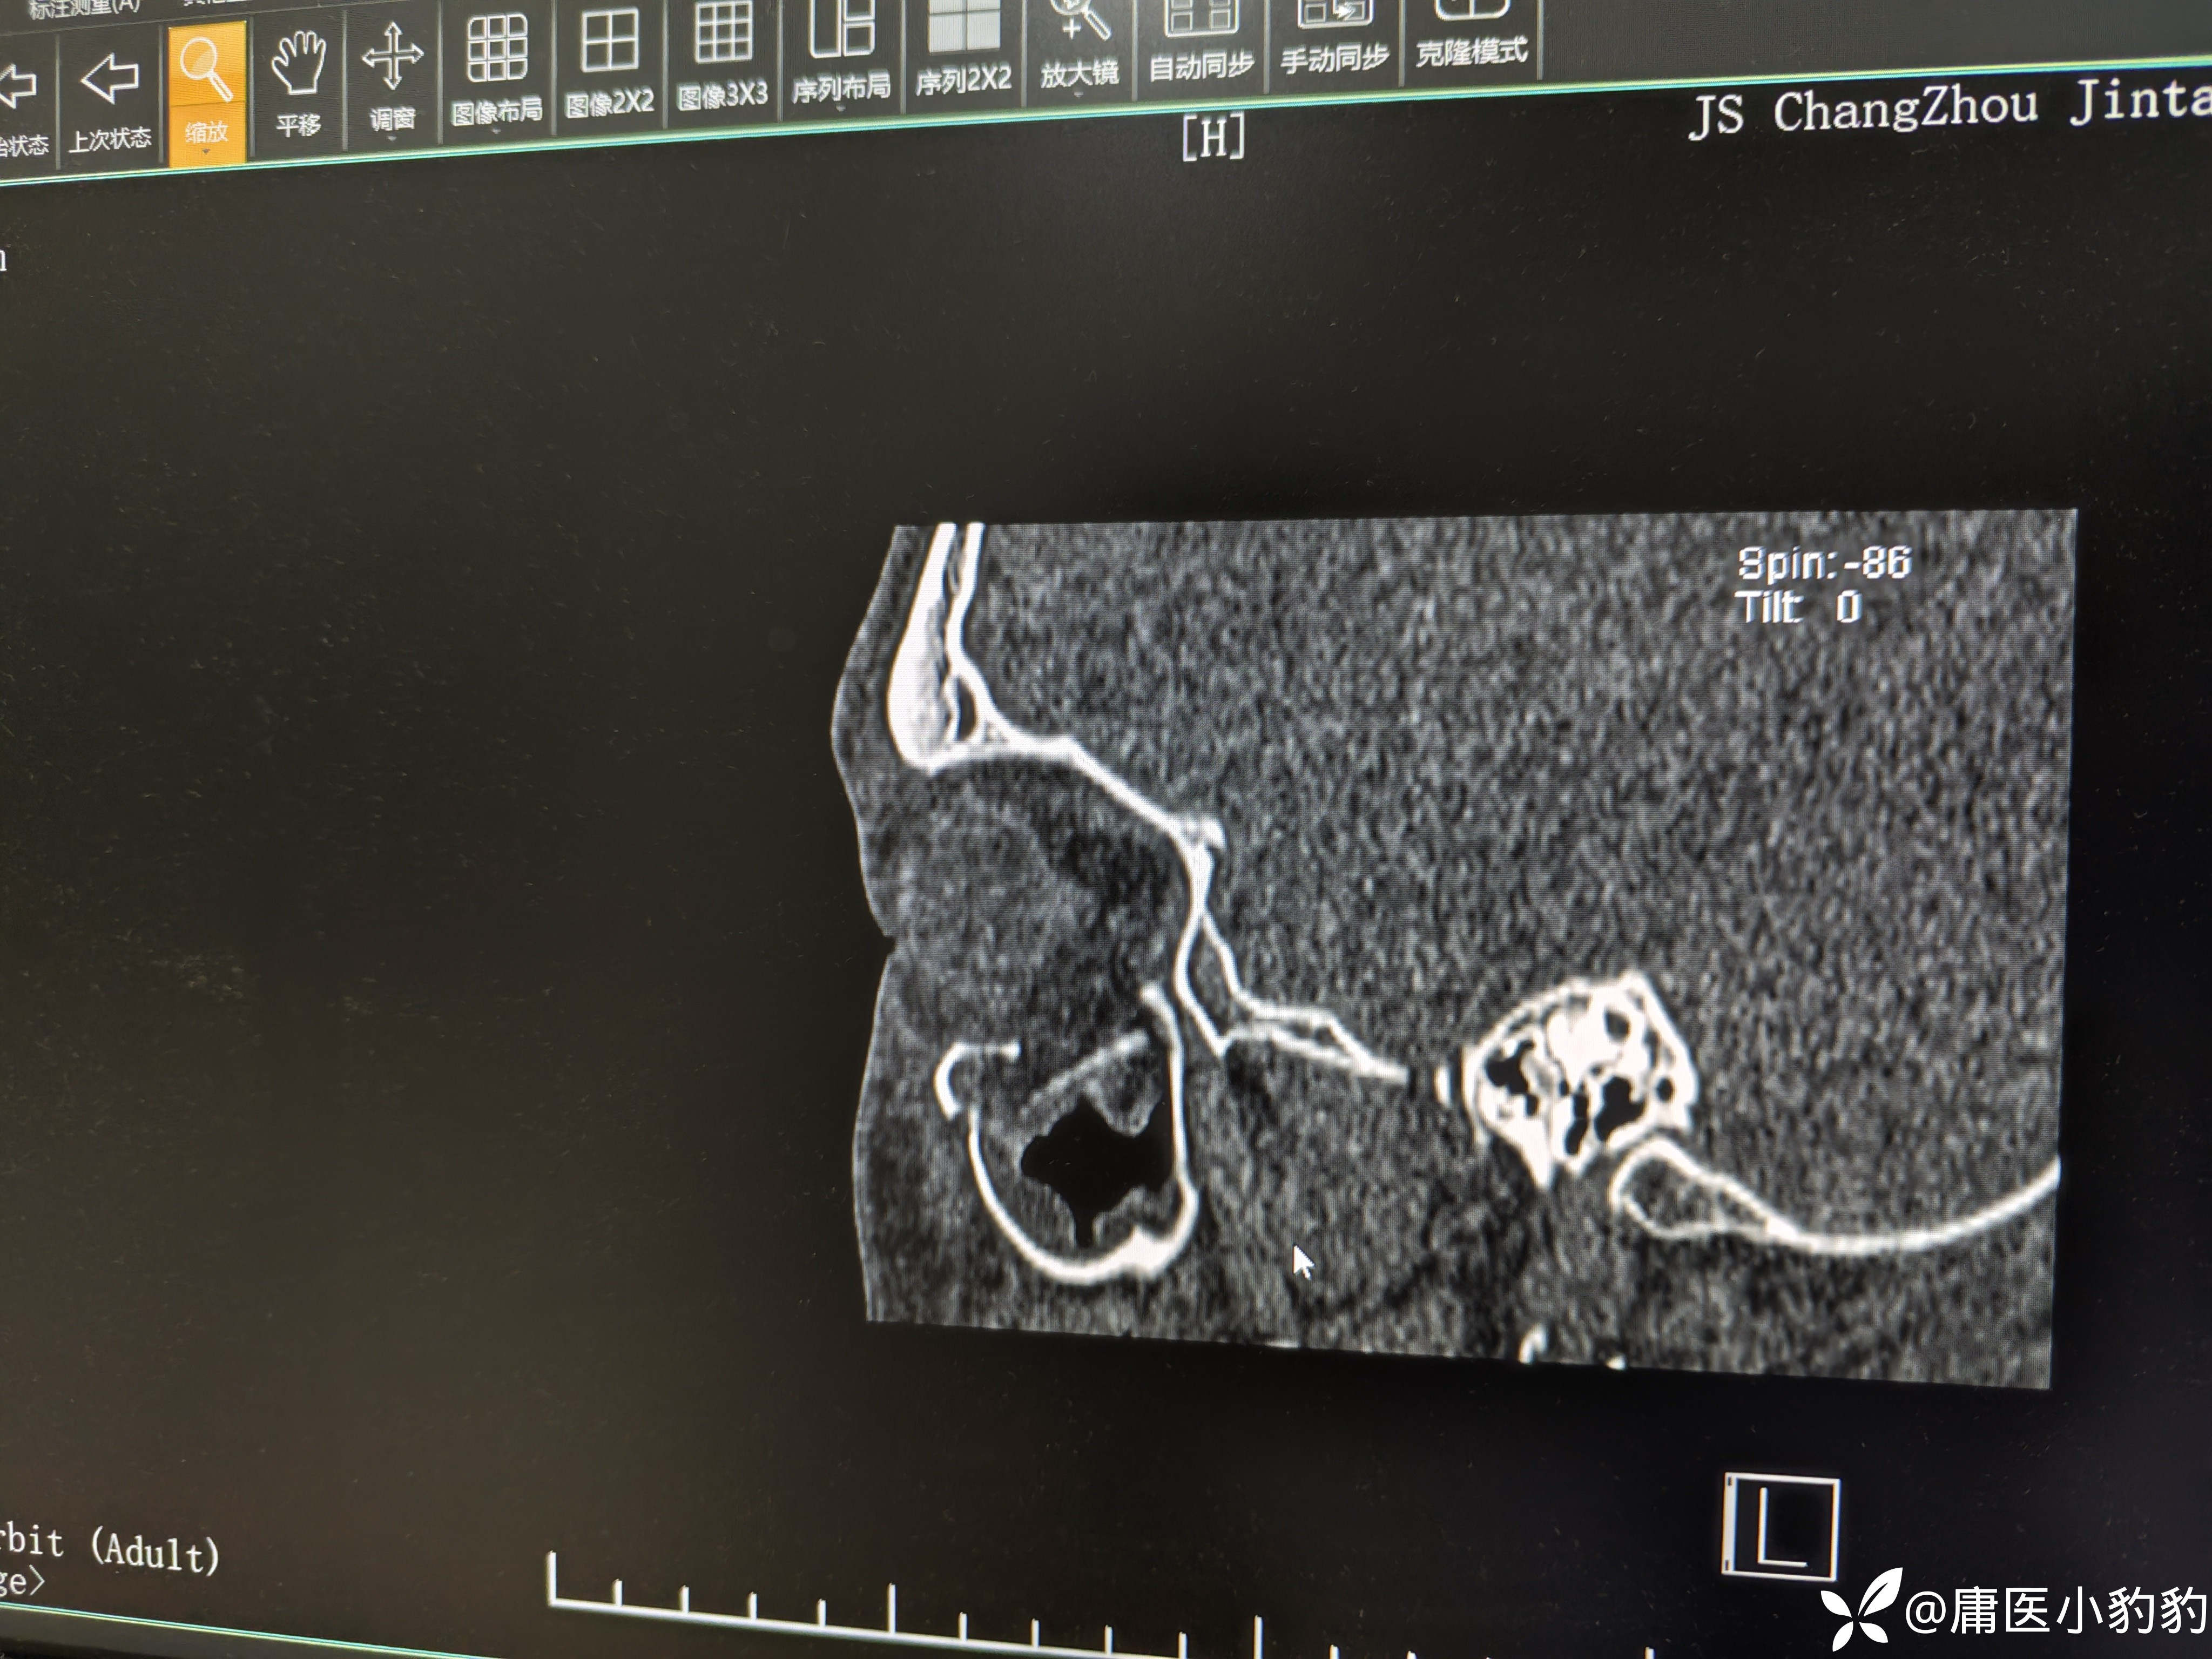

患者,男,26岁,五天前右面部外伤,右眼结膜下出血,主诉右眼视物模糊。眼眶CT示右上颌窦上壁骨折,右上颌窦内积血。眼科学检查示 矫正视力:右8.0/左1.0,眼压右18/左20,右眼视网膜震荡。无明显复视,重影,眼球运动未见明显受限,未行眼球牵拉试验。目前正在甘露醇+激素治疗观察。请问各位眼科的同门对该患者后续的治疗方案有何建议?